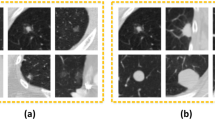

Lung cancer is one of the most common cancers in the world, and the detection and classification of benign-malignant lung nodules are critical during the diagnosis and treatment for lung cancer. In this paper, a multi-view improved dense convolutional network is proposed for the classification of benign-malignant pulmonary nodules, where more information of input multi-scale features can be extracted from 2D views of nine different directions. The improved dense block and other layers are linked by shortcuts, which optimizes the feature extraction. The proposed network model is trained in the LIDC-IDRI dataset, and the results show that the average classification accuracy and AUC are 86.52% and 97.23% respectively, which means that the network model has significantly improved the performance of benign-malignant pulmonary nodules classification.

Shen, LH., Wang, XH., Gao, MX., Li, B. (2021). Classification of Benign-Malignant Pulmonary Nodules Based on Multi-view Improved Dense Network. In: Huang, DS., Jo, KH., Li, J., Gribova, V., Bevilacqua, V. (eds) Intelligent Computing Theories and Application. ICIC 2021. Lecture Notes in Computer Science(), vol 12836. Springer, Cham. https://doi.org/10.1007/978-3-030-84522-3_48